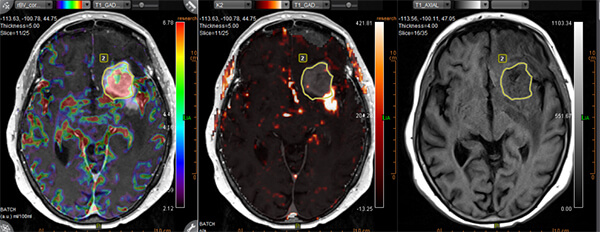

- Combination of special techniques with high-resolution anatomical images, providing additional information for tissue characterization (number of cells, blood flow and metabolic activity)

- Special Diffusion techniques (multiple b value DWI, IVIM)

- Perfusion (techniques: DSC, DCE, ASL)

- Spectroscopy